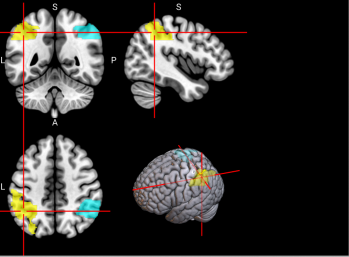

5,6

L & R Middle frontal gyrus (MFG)

Left middle frontal gyrus is involved in literacy and the right middle frontal gyrus is involved in numeracy [60].

/word/media/image9.png/word/media/image9.png